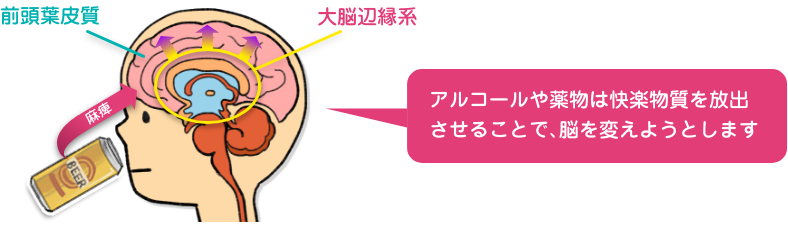

Operation Blue Wind 乱用 中毒 依存ってなに

Operation Blue Wind 乱用 中毒 依存ってなに

Operation Blue Wind 乱用 中毒 依存ってなに